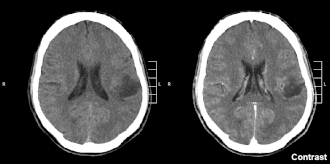

El glioma es un tipo de neoplasia que se produce en el cerebro o en la médula espinal. Se llama glioma, ya que surge a partir de células gliales. Su ubicación más frecuente es el cerebro.[1]